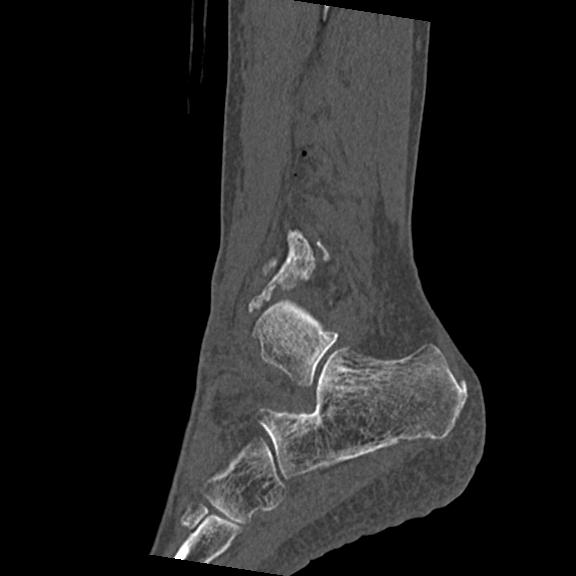

102755 1/4 2R 1/15 2R 右足関節 68歳女性 右三果脱臼骨折